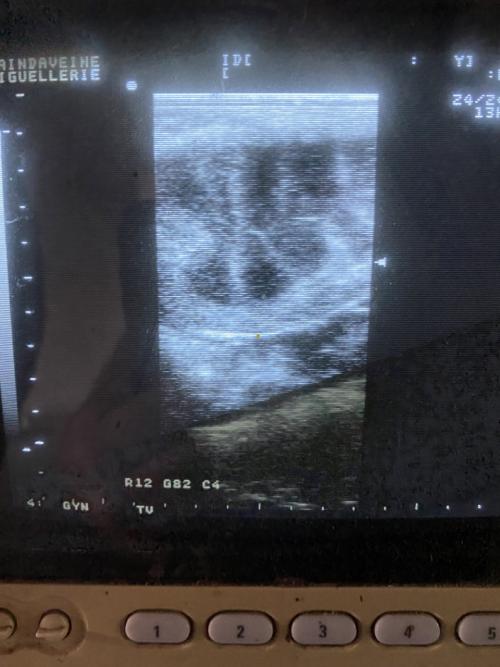

Image

Gynaecological monitoring is not limited to a simple insemination; it is a rigorous monitoring of the mare's reproductive tract. Our objective is twofold: to validate physiological suitability for breeding and to identify the optimal ovulatory window to maximize the chances of conception from the very first cycle.

The practitioner performs a comprehensive clinical and ultrasound evaluation, focusing on key structures:

• Ovaries: Monitoring of follicular dynamics to predict ovulation and detect any functional anomalies (persistent corpus luteum, cysts).

• Uterus: Assessment of uterine tone and environment. We pay particular attention to the absence of excessive post-ovulatory edema or endometritis, which are major factors in early failures.